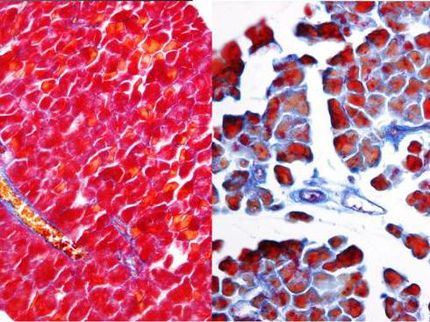

Células de un paciente con linfoma del manto antes (imagen izquierda) y despuas (imagen derecha) del tratamiento con el fármaco. Se observa inhibición del crecimiento celular.

IDIBELL